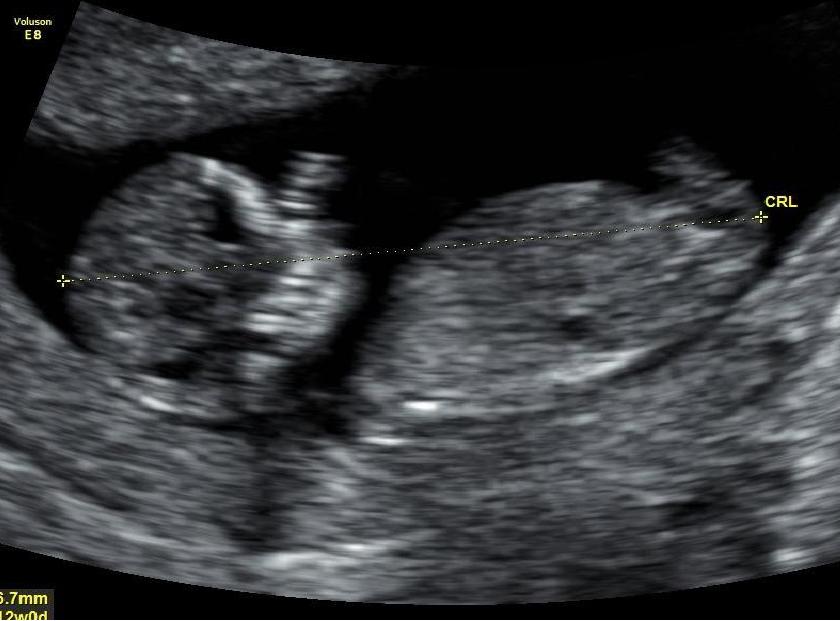

Hello All :) Last time I post this promise im just so excited to find out the gender.. Are there any Guesses on my babys 12 week ultrasound?? Il be sure to post the update on gender in here once I find out :) :)

Attachment 17439Attachment 17440Attachment 17441